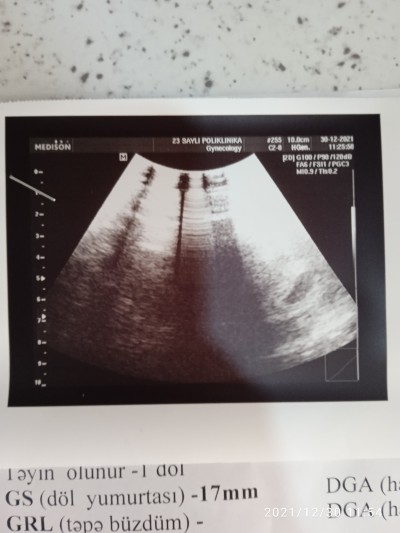

2hafta sora gel kalp atislarina bakalm dedi. Umarm onuda duyarm.5 haftalikmis

Bebeği arayıp buldum sağ tarafta çok minik annesi duyarsin insallah